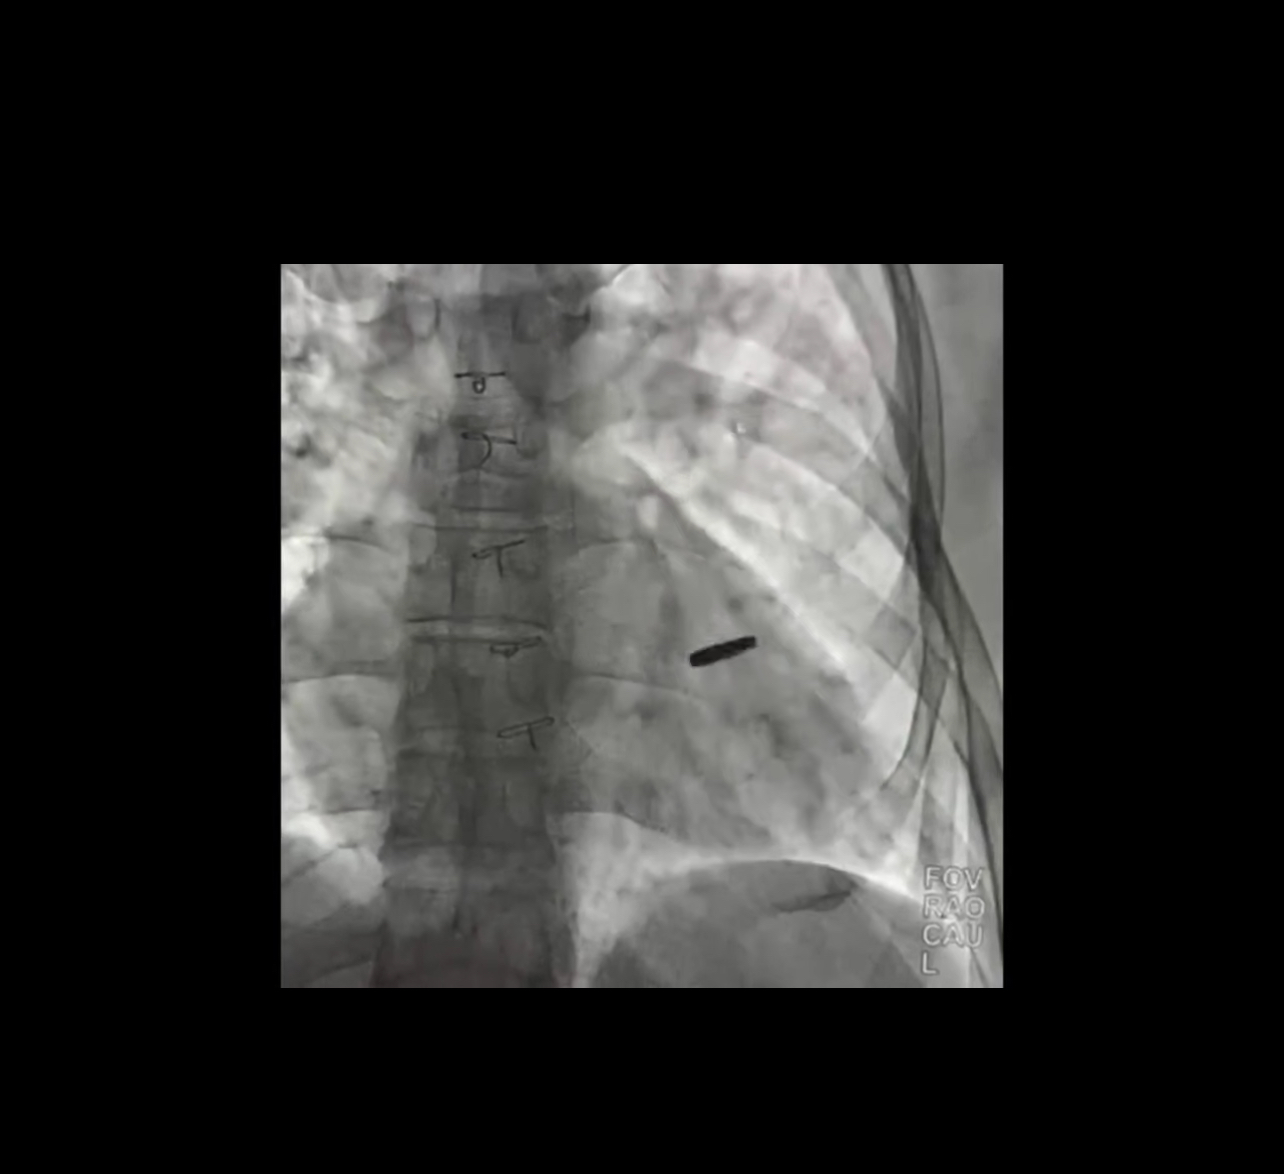

Три роки з кулею в серці: як оперували звільненого з полону захисника Азовсталі

Український захисник провів три роки у полоні РФ з кулею у серці.

У Києві успішно прооперували захисника “Азовсталі”, якого нещодавно звільнили.

Куля дивом не зачепила життєво важливі органи.

Зараз ми її видалили. Думаю, він проживе довге і щасливе життя, — сказав кардіохірург Інституту серця Борис Тодуров.